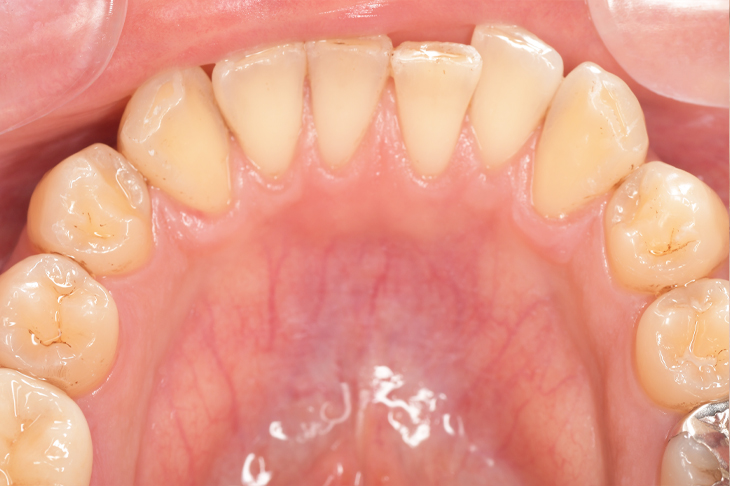

クリーニングの症例

現在の治療費と異なる場合がございます。最新の治療費は料金表をご確認ください。CASE 1

Before

After

基本情報

| 主訴 | 見た目をきれいにしたい |

| 治療期間 | 6ヶ月 |

| 治療費 | ジルコニアボンド(セラミックの被せもの)¥165,000×7(税込み) オフィスホワイトニング4回 ¥4,400×4(税込み) ホームホワイトニング¥11,000 |

| リスク・副作用 | かみ合わせがとても強い方の場合、稀に割れてしまうことがあります。 |

| 先生からの提案 | 上の前歯6本と右下の2番目の歯はセラミックの被せもので治療。 残りの下の前歯5本はプラスチックの材料で虫歯を治療し、 ホワイトニングをおこないました。白くなったご自身の歯の色に合わせてセラミックの 被せものを作成しています。 模型上で完成後をシュミレーションし、上の歯茎の位置をきれいに見えるように 揃えています。(外科処置はしていません) |